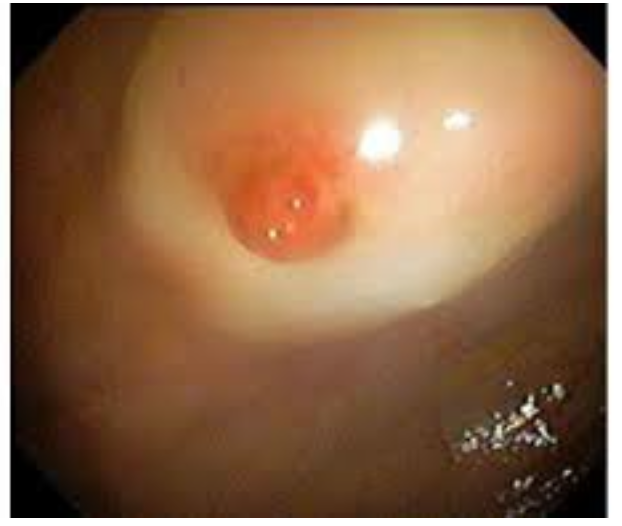

Dieulafoy lesion